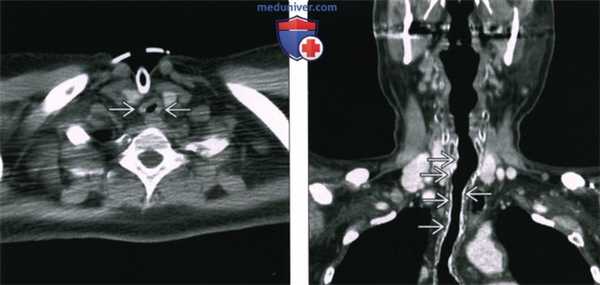

(Слева) КТ с КУ, аксиальная проекция. Пациент спустя четыре месяца после химиолучевой терапии по поводу плоскоклеточного рака гортаноглотки. Правый черпаловидный хрящ склерозирован, позади него имеется газ и мягкие ткани.

(Справа) КТ с КУ, аксиальная проекция, этот же пациент три месяца спустя. Аутоампутация правого черпаловидного хряща, от которого остался лишь небольшой костный останок. Отек в гортаноглотке значительно менее выражен. Данные признаки характерны для неопухолевого радионекроза черпаловидного хряща и тканей гортаноглотки. Хондронекроз является одним из осложнений лучевой терапии.